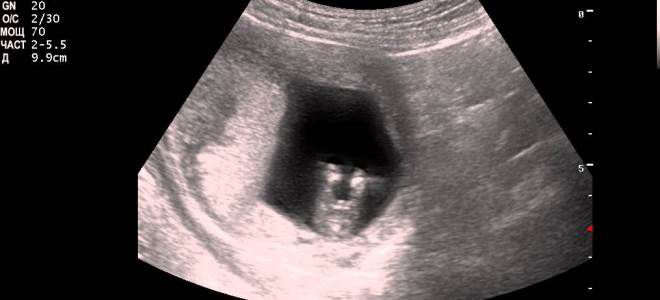

УЗИ, первый триместр

Ультразвуковое исследование (УЗИ) в первом триместре беременности осуществляется не ранее 11 акушерских недель и не позднее 14. Основная цель данного обследования заключается в оценке физических параметров развития плода и выявлении возможных аномалий в его строении. При проведении УЗИ в первом триместре учитываются следующие ключевые параметры:

- КТР – копчико-теменной размер (расстояние от теменной кости до копчика);

- окружность головы;

- БПР – бипариетальный размер (расстояние между теменными буграми);

- ТВП – толщина воротникового пространства;

- частота сердечных сокращений (ЧСС);

- длина плечевых, бедренных костей, предплечья и голени;

- расположение сердца и крупных кровеносных сосудов;

- положение плаценты, место ее прикрепления и толщина.

УЗИ в первом триместре беременности – нормы

Ультразвуковое исследование, проводимое на ранних сроках беременности (первый триместр), предназначено для выявления возможных аномалий в развитии плода. В процессе обследования врач определяет ключевые параметры физического развития малыша, которые в норме должны соответствовать следующим значениям:

- КТР (кокцигиально-теменной размер):

- На 10-й неделе беременности – 33–41 мм;

- На 11-й неделе – 42–50 мм;

- На 12-й неделе – 51–59 мм;

- На 13-й неделе – 62–73 мм.

- ТВП (толщина воротниковой зоны):

- На 10-й неделе – 1,5–2,2 мм;

- На 11-й неделе – 1,6–2,4 мм;

- На 12-й неделе – от 1,6 до 2,5 мм;

- На 13-й неделе – 1,7–2,7 мм.

- ЧСС (частота сердечных сокращений, удары в минуту):

- На 10-й неделе – 161–179;

- На 11-й неделе – 153–177;

- На 12-й неделе – 150–174;

- На 13-й неделе – 147–171.

- БПР (бипариетальный размер):

- На 10-й неделе – 14 мм;

- На 11-й неделе – 17 мм;

- На 12-й неделе – 20 мм;

- На 13-й неделе – 26 мм.